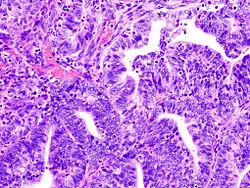

![]() Endometrialny gruczolakorak naciekający mięsień macicy | |

Typ I

Zazwyczaj rak endometrialny składa się z okrągłych lub owalnych gruczołów ograniczonych komórkami nabłonkowymi z zachowaną polarnością. Obecność dużych mas komórek nieformujących się w gruczoły świadczy o wyższym gradingu nowotworu.

- Grade I: lite masy stanowią <5% nowotworu

- Grade II: lite masy stanowią 5-50% nowotworu

- Grade III: lite masy stanowią >50% nowotworu[5]